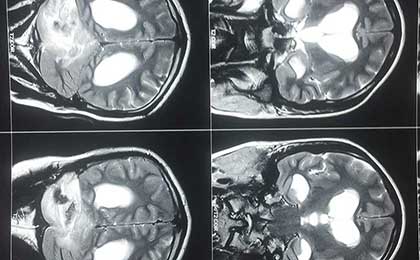

Obstructive Hydrocephalus 2 Pre Op Mri